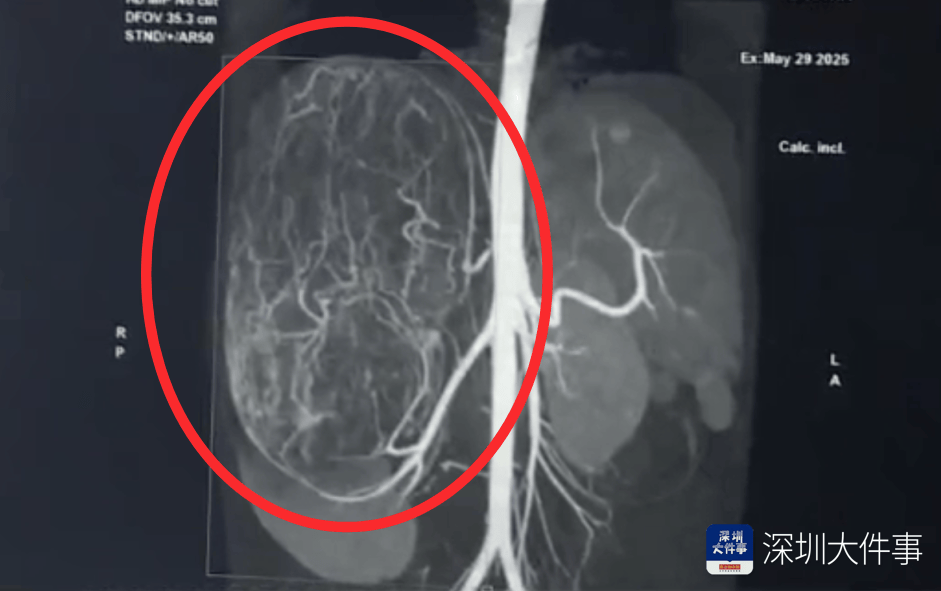

影像检查结果出来,所有人都倒吸一口冷气:一个直径27厘米(比篮球还大)的巨型肿瘤,霸占了整个腹腔右半边项链。肝脏被它硬生生挤到了肚脐眼以下的位置!

肿瘤体积过大,这也意味着留给医生的手术空间实在有限,强行微创?万一瘤子破了,肿瘤扩散大出血,后果不堪设想!所以,只能通过开放手术来做项链。

5月30日,医生为婷婷做手术,打开腹腔后,医生遇到了挑战:婷婷的肾动脉异于常人:正常人就1根肾动脉供血,她居然有3根项链。还有一支来自腹腔干动脉,一支来自腰动脉。

这三根“命脉”就盘踞在巨大的瘤体上,稍有不慎,剪错一根,就可能引发大出血项链。

手术团队屏气凝神,抽丝剥茧,一根一根精准找到、小心分离、稳稳阻断……经过3个多小时的精密操作:重达2.43公斤直径达27厘米的“巨无霸”肿瘤被完整端出项链。周围需要清扫的淋巴和脂肪组织也被清除。